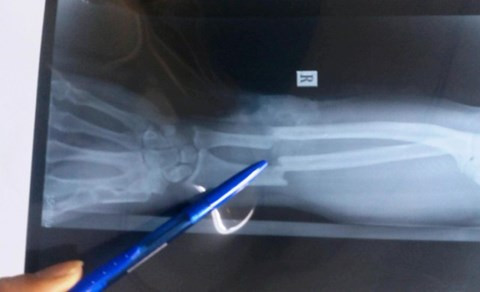

Về tình trạng của nạn nhân, trao đổi với phóng viên, bác sĩ Nguyễn Hồng Hà – Đại diện bệnh viện Nhân dân Gia Định, quận Bình Thạnh cho hay, ca phẫu thuật nối cánh tay phải gần đứt lìa của ông Đỗ Thanh Bình (SN 1975, ngụ quận 1) diễn ra hết sức khó khăn, phải mất hơn 6h (từ 17h chiều đến hơn 22h đêm 21/10) mới hoàn thành. Nguyên nhân vì bệnh nhân đứt lìa xương cẳng tay phải và chỉ còn dính với nhau bằng một phần mềm rất nhỏ; bó mạch máu, thần kinh cẳng tay bị đứt phải thực hiện vi phẫu, mất nhiều máu. Hiện bệnh nhân đã qua cơn nguy kịch.

Cánh tay phải gần đứt lìa khi chụp X-Quang.